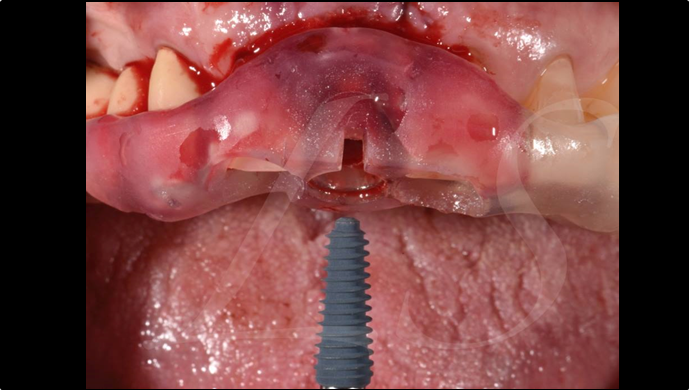

“ One implant /One tooth/ One hour step-by-step

+ associated connective graft ”

Clinical case: EImmediate implant placement & loading of #35 extraction socket with defect

- Courtesy of Dr. Kwang Bum Park, Korea -